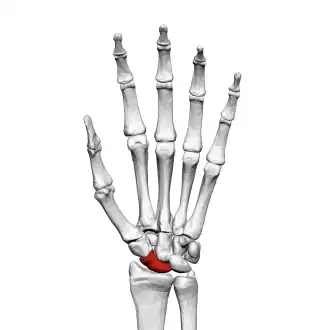

The scaphoid bone is one of the carpal bones of the wrist. It is situated between the hand and forearm on the thumb side of the wrist (also called the lateral or radial side). It forms the radial border of the carpal tunnel. The scaphoid bone is the largest bone of the proximal row of wrist bones, its long axis being from above downward, lateralward, and forward. It is approximately the size and shape of a medium cashew nut.

The scaphoid is situated between the proximal and distal rows of carpal bones. It is located on the radial side of the wrist,[1]: 176 adjacent to the styloid process of the radius.[2] It articulates with the radius, lunate, trapezoid, trapezium, and capitate.[1]: 176 Over 80% of the bone is covered in articular cartilage.[3]

![]() Left hand anterior view (palmar view). Scaphoid bone shown in red. | |